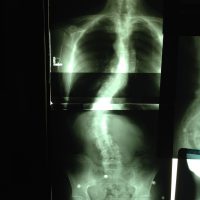

Dooley Noted: 3/14/2015 Take a look at the spinal and pelvic radiographs of my friend and colleague, Lynne Ellen Kershaw. You want to see these. Go ahead. I’ll wait. Now, I want you to attempt a guess at where she experiences discomfort. Look closely again at the structures. Think you’ve got it? Lynne Ellen has pain nowhere. She feels amazing. She is 61 years old, with idiopathic scoliosis. She works 14 hours a day, … Read more